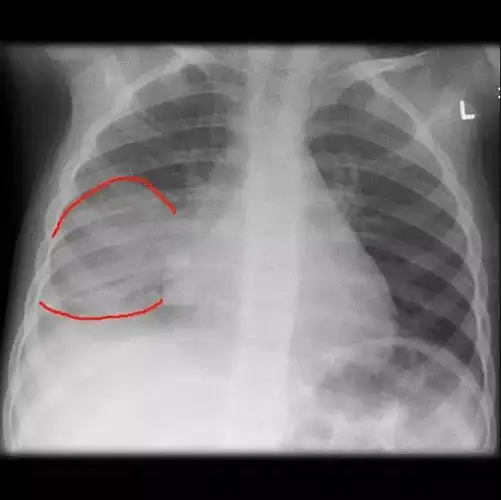

儿童肺炎时胸片怎么看呢